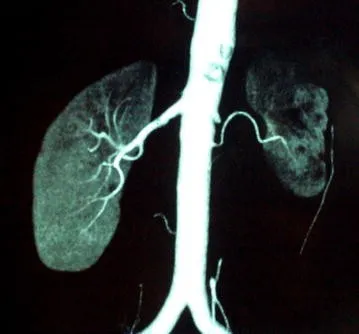

O paciente está congesto? O que realmente ajuda na prática?

O paciente está congesto? O que realmente ajuda na prática?